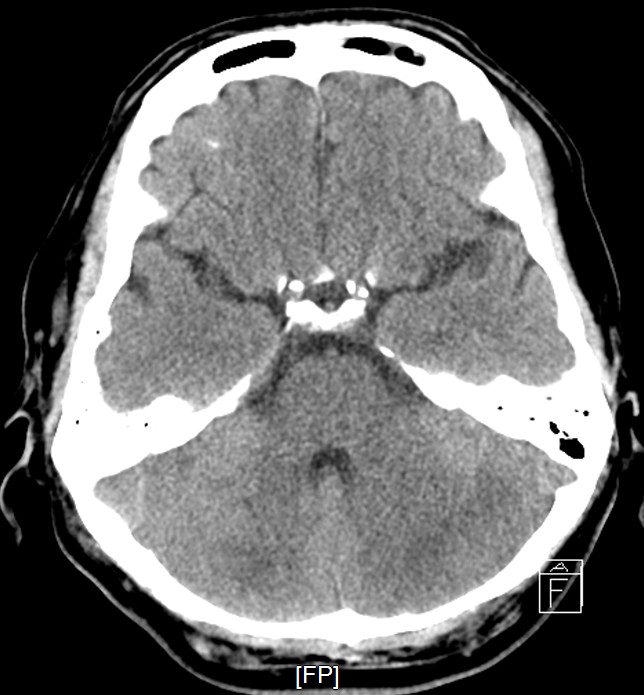

Staged PCI (Mar 6): One DES was placed in the LCX and one DCB in the LM–LCX segment. ECMO and IABP were successfully removed on March 8. Continuous renal replacement therapy was started for acute kidney injury. Brain CT showed watershed infarcts and a small subarachnoid hemorrhage, followed by gradual neurological recovery.